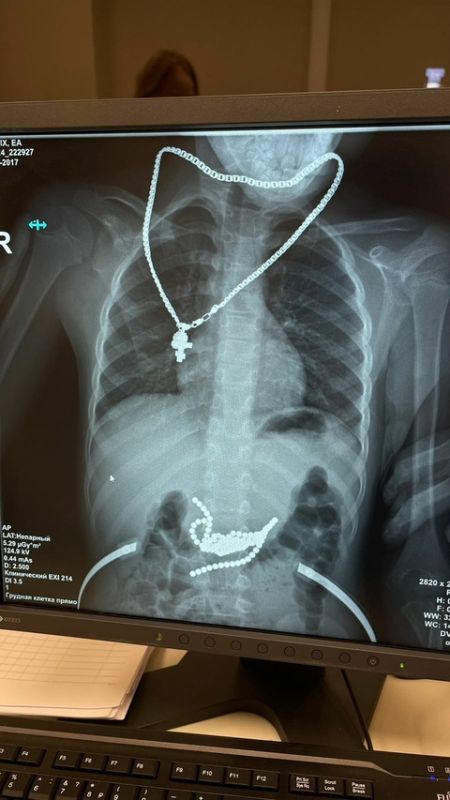

50 магнитных шариков достали хирурги из желудка маленького пациента в ростовской клинике. Мальчик проглотил детали опасной игрушки, развивающей мелкую моторику, и не спешил рассказывать об этом родителям, сообщили в пресс-службе ростовской областной детской больницы.

Узнав о произошедшем, родители поспешили в больницу. Рентген показал, что магнитные шарики уже начали притягиваться друг к другу, вызывая предперфорацию стенки желудка и 12-перстной кишки. Если бы ребёнок рассказал о случившемся на пару часов позже, последствия были бы гораздо серьёзнее.

Чтобы достать детали игрушки, врачи вскрыли желудок и кишечник малыша. Неодимовые шарики, обладающие самой большой силой магнетизма, успешно извлекли.